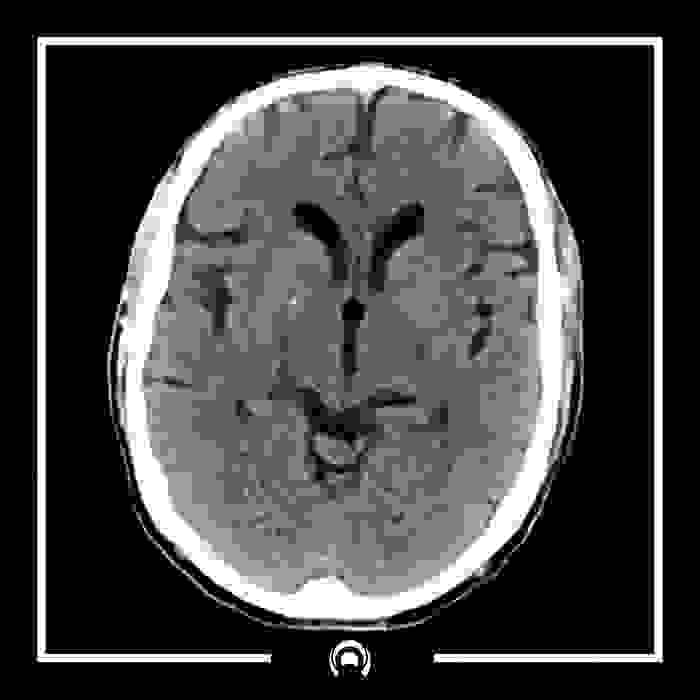

Tomografía de Cráneo

La tomografía computarizada (TC), un tipo de radiografía, obtiene imágenes detalladas que, al combinarse, crean una imagen tridimensional de las estructuras internas de la cabeza. Algunas exploraciones utilizan un medio de contraste para que los vasos sanguíneos y los tejidos se visualicen mejor. En algunas personas, el contraste intravenoso puede causar una reacción alérgica o afectar la función renal, especialmente en quienes padecen enfermedad renal. Si tiene problemas renales, informe al equipo de diagnóstico por imágenes.

Si recibe una inyección de contraste antes de la exploración, puede experimentar una sensación de calor en todo el cuerpo o un sabor metálico en la boca. Ambos síntomas desaparecerán pronto. La exploración en sí produce una mayor exposición a la radiación que una radiografía típica, pero el riesgo de problemas de salud derivados de una sola tomografía computarizada (TC) de la cabeza es extremadamente bajo.